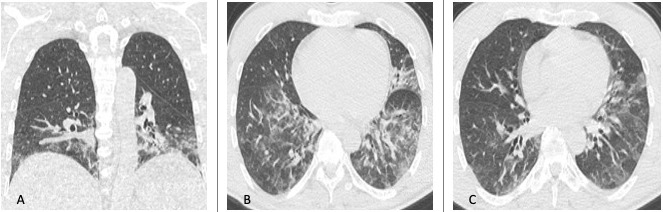

Figura 9: Uomo di 65 anni giunto al Pronto Soccorso dopo aver rischiato la morte per annegamento. La TCAR eseguita all’ingresso (immagini assiali A-B-C e ricostruzione MPR coronale D) mostra la presenza di aree di aumentata densità con aspetto a "vetro smerigliato" in entrambi i polmoni con associato ispessimento liscio dei setti interlobulari con tipica distribuzione gravitazionale.

Figura 10: Donna di 53 anni bracciante agricola, giunge al Pronto Soccorso per febbre, dispnea ingravescente, tosse e mialgia. La TCAR eseguita all’ingresso (A e B) mostra "vetro smerigliato" diffuso cui si associano aree di ipodensità parenchimale e aree di parenchima normale in rapporto a "three density" pattern. Le scansioni effettuate in espirazione (C e D) mostrano inoltre la presenza di aree di intrappolamento aereo. L’ipotesi diagnostica formulata (in seguito confermata) in considerazione dei reperti TC e dell’anamnesi lavorativa della paziente è stata quella di polmonite da ipersensibilità in fase acuta/subacuta non fibrosante.

Figura 11: Uomo di 68 anni giunge in Pronto Soccorso per grave dispnea, IRA e febbre, esegue TC TORACE all’ingresso nel sospetto di polmonite da SARS-CoV-2. La TCAR (scansioni assiali A-B-C-D) documenta ispessimento liscio dei setti interlobulari in entrambi i polmoni più evidente in sede perilare e nei lobi inferiori ove si associa la presenza di alcune aree di aumentata densità con aspetto a "vetro smerigliato" maggiori a destra. Si associa falda di versamento pleurico bilaterale. L’ipotesi diagnostica formulata ed in seguito clinicamente confermata è stata quella di alterazioni di natura emodinamica.